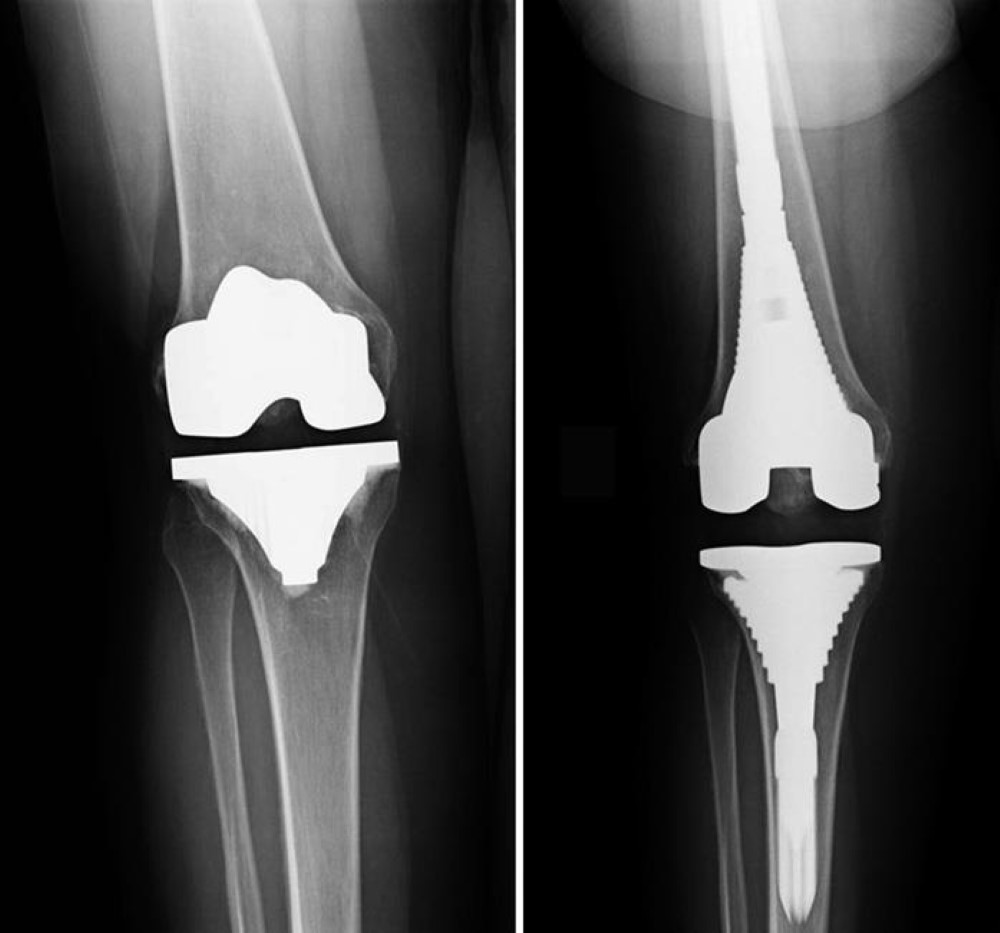

-> Fracture fixation (plates, screws, rods)

Treatment depends on the fracture type and may include immobilization with casts or splints, closed reduction (non-surgical alignment), surgical fixation with plates, screws or rods, and follow-up rehabilitation to restore movement and strength.